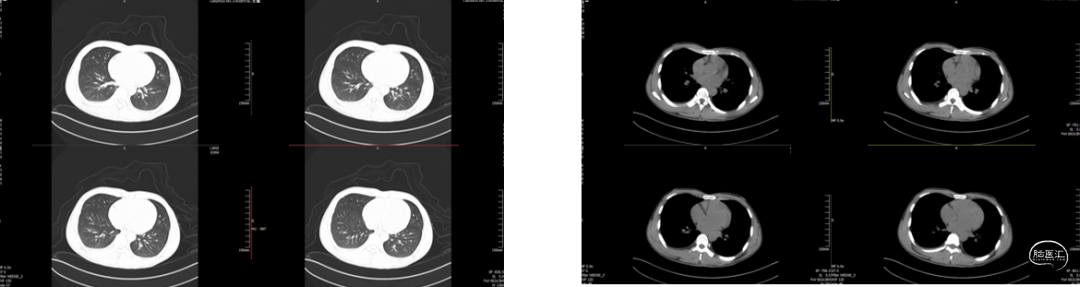

现病史:患者于入院前2小时在工地干活时被高空坠物砸伤头部(具体过程不详),伤后出现左侧肢体活动失灵,被同事送往我院急诊科就诊,入急诊时神志清醒,GCS15分,行颅脑CT提示:1. 右侧颞顶骨骨折,顶骨多发骨折并部分嵌插脑内;2. 右侧顶叶脑挫伤;3. 右侧额颞顶部硬膜下血肿;4. 蛛网膜下腔出血。急诊予以清创、止血及对症治疗。期间患者意识障碍加重呈嗜睡,GCS14分,我科急会诊后以“1. 开放性颅脑损伤特重型 1.1开放性颅内异物1.2脑挫裂伤1.3蛛网膜下腔出血1.4颞顶骨骨折(右);2. 偏瘫(左)”收住入院。自发病来,患者暂无抽搐、晕厥等症状,小便失禁。

入院检查

![]()